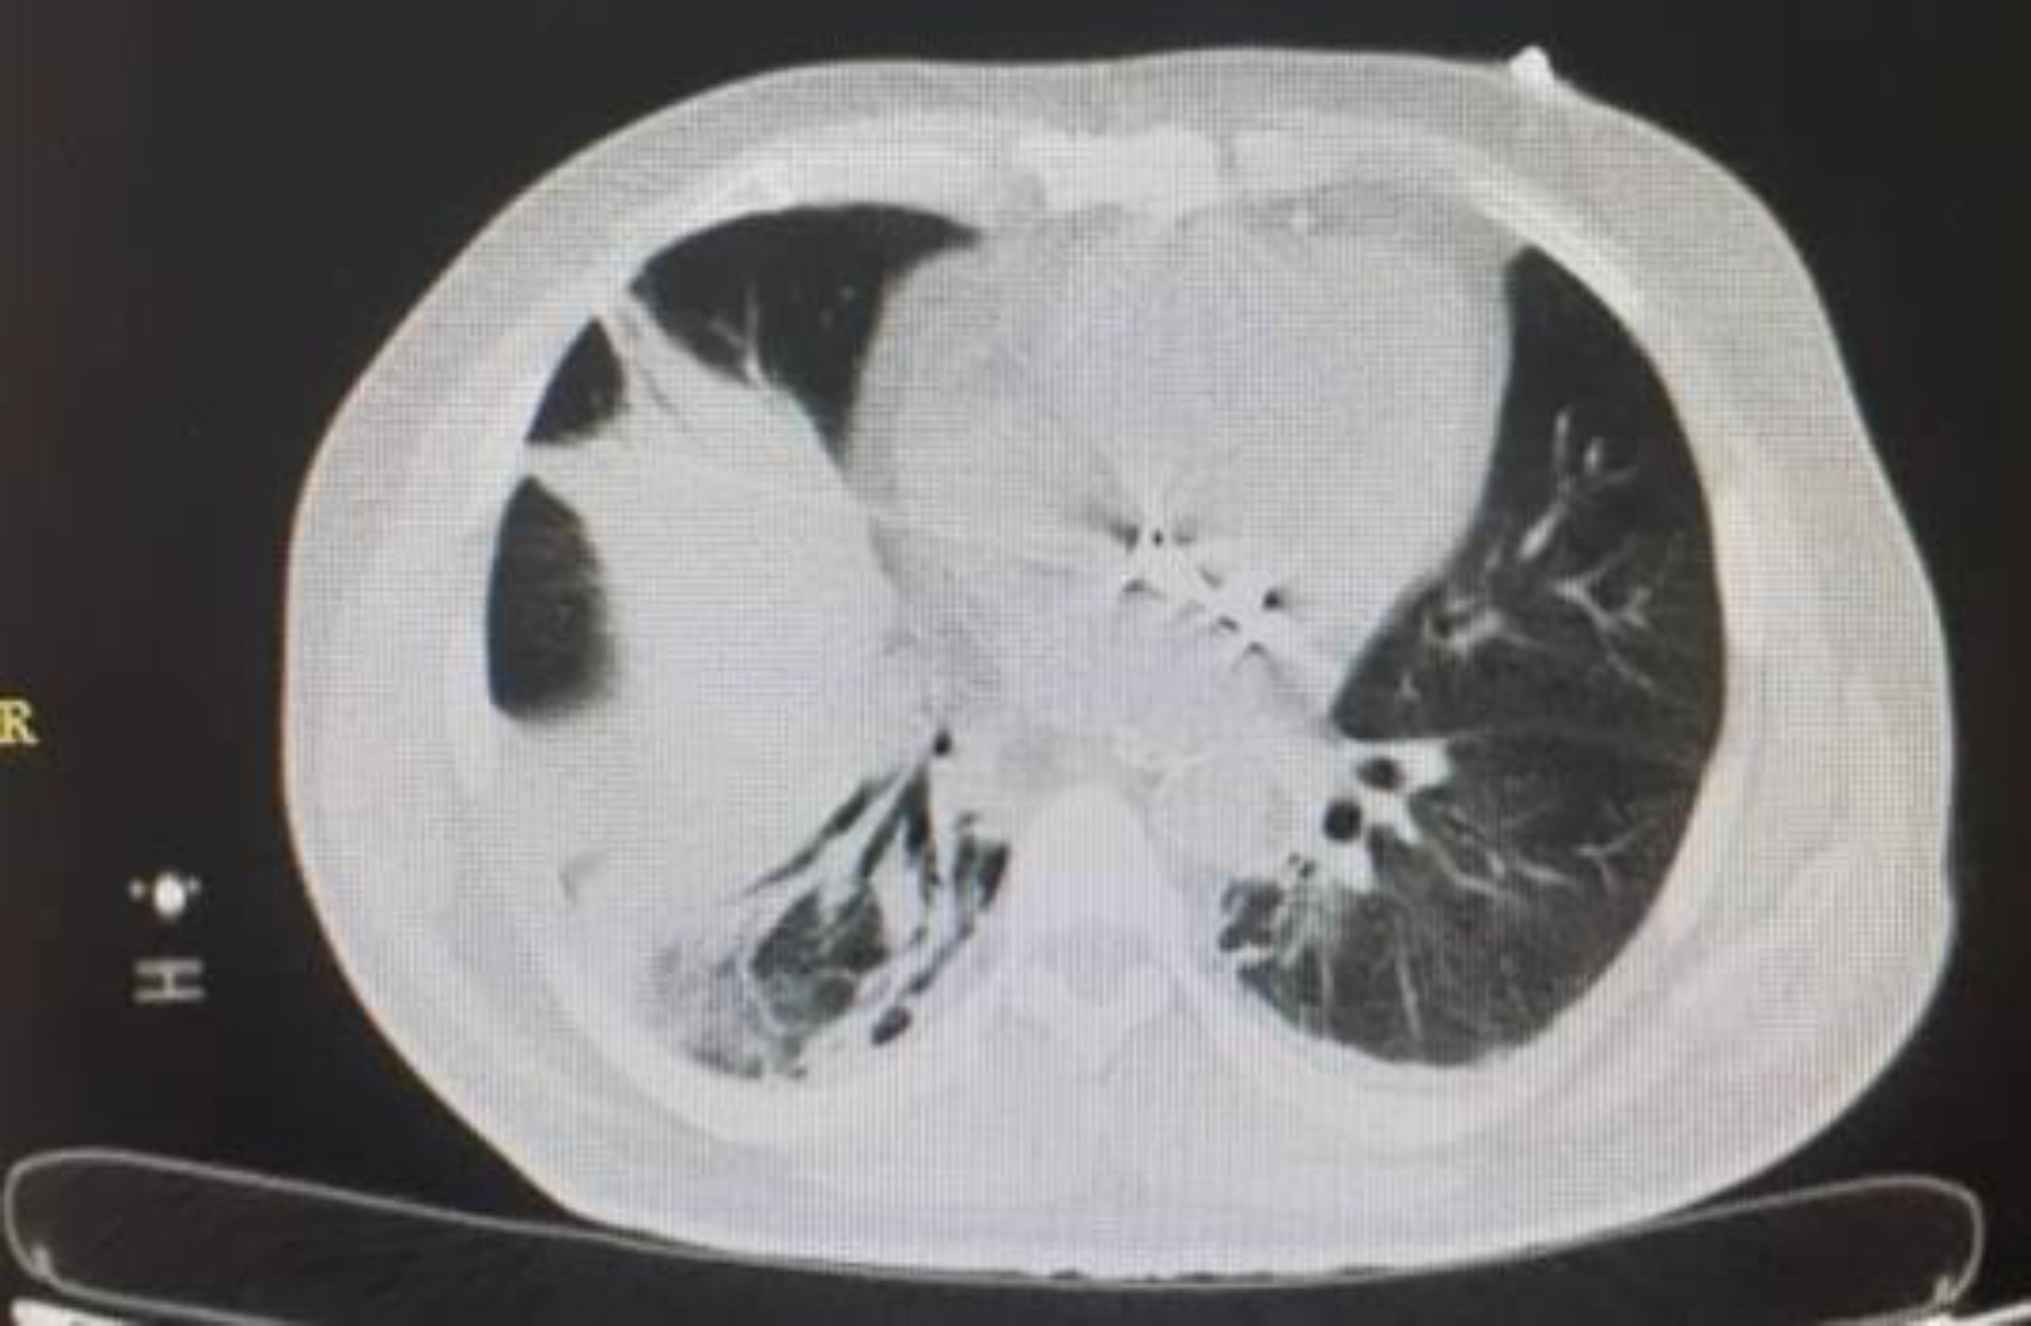

A 58-year-old man with COVID-19 confirmed by RT-PCR and chest computed tomography (CT) scan (Figure 1) was referred to the emergency department with a history of mitral valve replacement, hyper-tension, and complaint of generalized abdominal pain and dyspnea. Vital signs on admission time were as follows: blood pressure (BP) 140/70 mm Hg, pulse rate (PR) 120/min, temperature 37.3°C (oral), and oxygen saturation (SpO2) 92% in room air. He had a relative decrease in white blood cell (WBC) count. On abdominal examination, he had tenderness in the right lower quadrant (RLQ) without any guarding and rebound tenderness. He used warfarin due to cardiac problems; the international normalized ratio (INR) was 8 upon arrival, and no cardiac thrombosis was seen on his echocardiogram. After an abdominal CT scan due to abdominal pain, mesenteric ischemia was diagnosed. After correction of INR with transfusion of fresh frozen plasma (FFP), surgery was planned for him. During the surgery, 140 cm of the small intestine in the ileum was ischemic (Figures 2 and 3). After the operation, he suffered a drop in SpO2 and BP that led to his death.

Fig. 1.Lung involvement with COVID-19